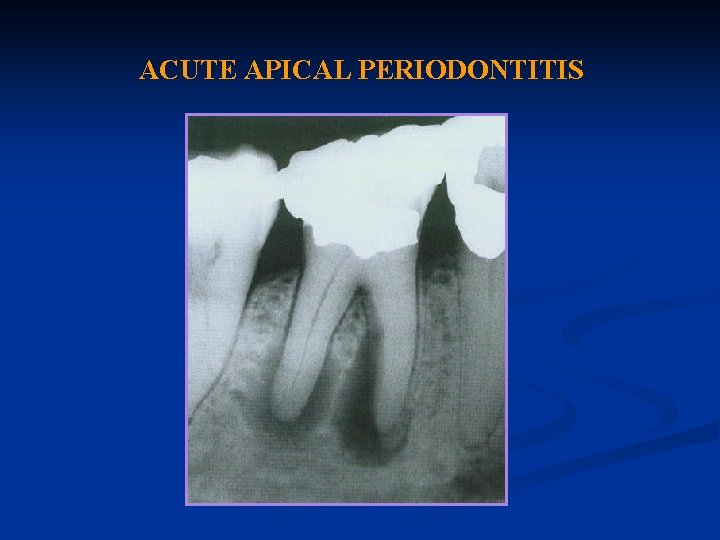

ACUTE APICAL PERIODONTITIS

Acute Apical Periodontitis: Definition Acute apical periodontitis is a painful inflammation of the periodontium as result of trauma, irritation, or infection through the root canal, regardless of whether the pulp is vital or nonvital.